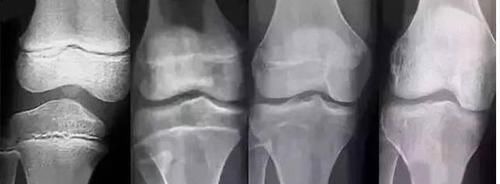

第二天,西西的母亲带着孩子去医院检查,西西虽然现在个子不矮,但是骨龄已经超前发育了,孩子的股侯倩可能会提前闭合,长不了很高了。不难发现,越来越多的小女孩患有性早熟,而且女孩比男孩多。这是因为女孩比男孩更容易受到刺激,接受刺激后会分泌雌激素,儿童会慢慢患上性早熟。家里有女孩的父母必须提前采取预防措施,做好预防。